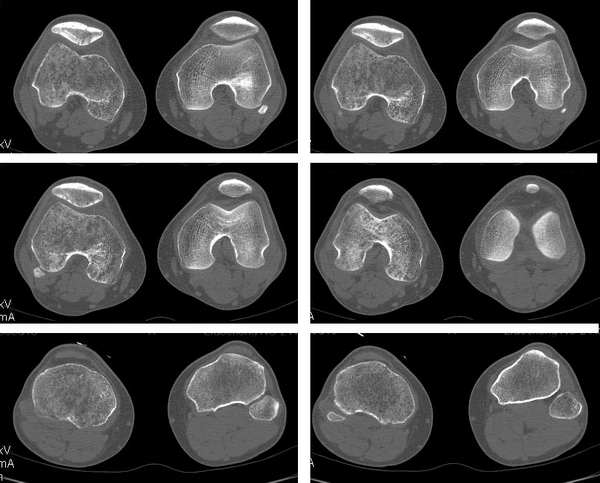

右侧股骨下端 胫骨近端及髌骨见骨质疏松,松质及皮质见虫蚀状溶骨性破坏,皮质变薄,骨小梁减少模糊,胫骨近侧干骺端内侧骨破坏性,关节肿胀,关节间隙增宽,周围未见明显软组织肿块.

就膝关节的病变,我还是支持wawaquan版主的意见,病理上可以解释为长期的关节炎性病变,充血引起的骨质疏松!!多发骨髓瘤好发于扁骨,再说,发生于长骨的多为一骨多病灶,象这样关节两端,骨质改变相同的少见!软组织变化也不支持.

考虑为缺血性改变。股骨远端及胫骨近端均呈同样改变,髓腔及骨皮质均未见骨破坏改变。

无积液,皮质变薄、小梁纤细无中断,骨干变细,周围肌群明显萎缩,不支持mm,也不支持滑膜慢性充血所致骨质疏松,故首先考虑废用性局限性骨质疏松,请结合临床查找疼痛原因。